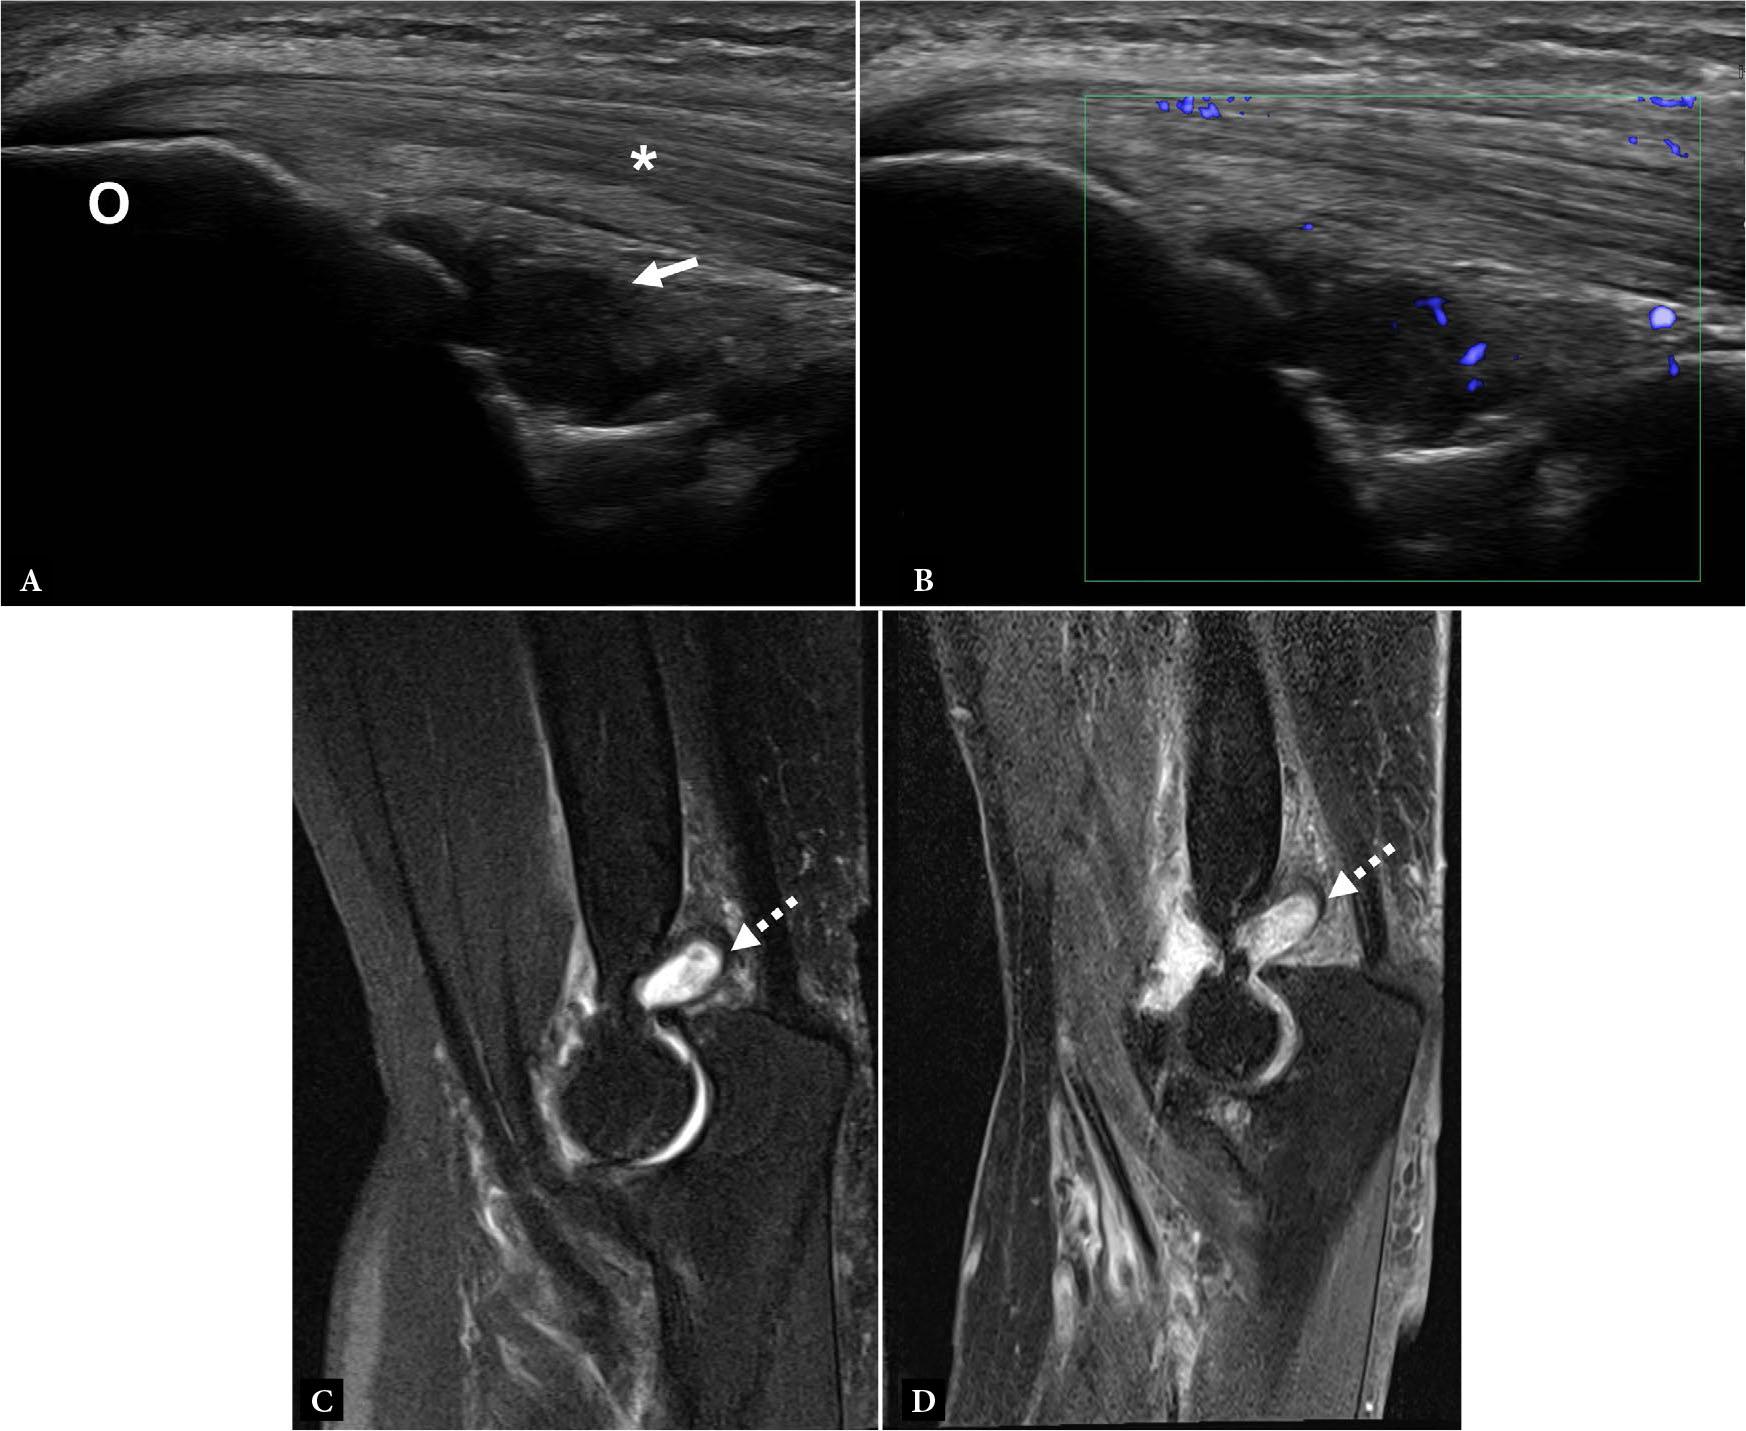

Fig. 2.